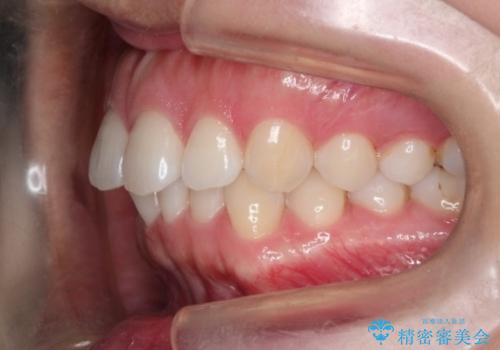

【前歯のガタガタが気になる】インビザライン症例

- 前歯の歯並びの改善を希望され来院された患者様です。

初診時の歯並びの状態としては、下顎前歯に及ぶの中等度のがたつき(叢生)があり、前歯が深く噛みこんでいる状態でした。

抜歯は行わず歯列弓の拡大やディスキング(歯と歯の間の隙間を作る処置)を行い叢生を改善しました。

矯正装置としてはマウスピースを使用しています。